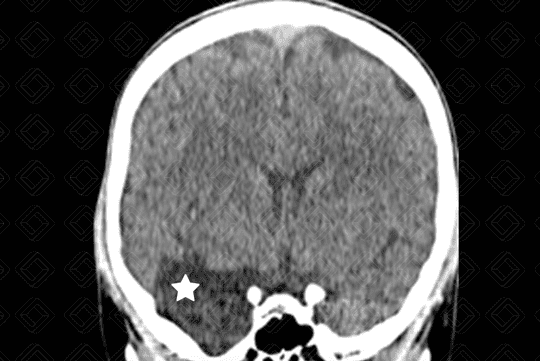

Descrição da lesão: Tomografia computadorizada do crânio. Lesão hipodensa, extra-axial, com densidade semelhante ao liquor, na fossa craniana média, deslocando o lobo temporal direito posteriormente (asterisco).

Cisto aracnoide: Caracteriza-se por uma expansão meníngea, em forma de bolsa, preenchida por líquido, com densidade semelhante ao liquor, mais comumente diagnosticada nas crianças e adultos jovens, sendo frequentemente um achado de imagem. Sua localização mais comum é na fossa craniana média (50-60% dos casos), mais especificamente na região temporal, adjacente à fissura sylviana. Outras localizações menos comuns são ângulo pontocerebelar e suprasselar (10% cada).

• Tomografia computadorizada do crânio: Lesão extra-axial, hipodensa, com densidade semelhante ao liquor e sem realce pelo meio de contraste. Pode ocorrer remodelamento ósseo da calota craniana adjacente à lesão, especialmente na população pediátrica;